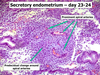

What day of the menstrual cycle is this?

What day of the menstrual cycle is this?

What day of the menstrual cycle is this?